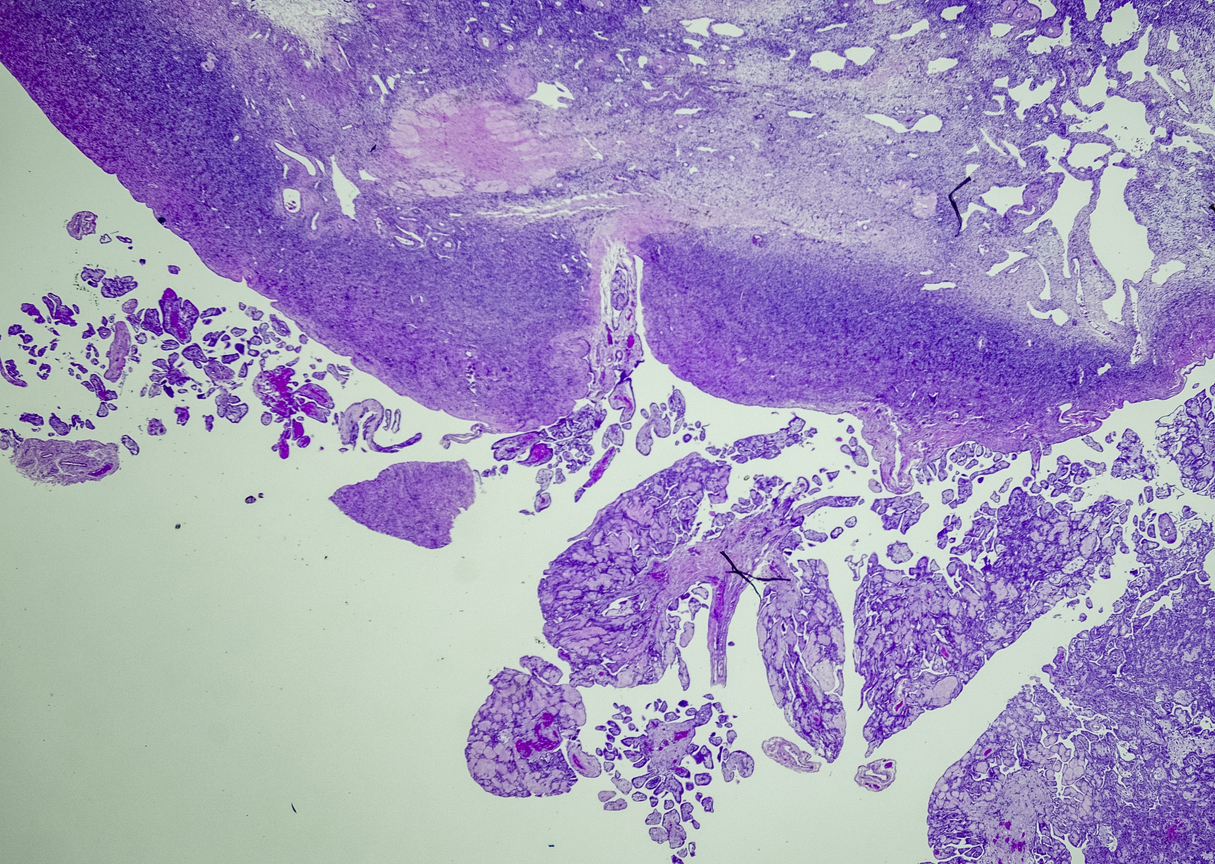

A tissue biopsy is the only way to diagnose epithelioid mesothelioma. This procedure involves taking samples of suspicious tissue. Pathologists examine the tissue samples under a microscope to identify specific cell characteristics.

Epithelioid mesothelioma cells clump together in groups and don’t tend to travel. These cell types are less likely to spread to other areas of the body. When a pathologist confirms the presence of specific cancer cells, an accurate diagnosis of your mesothelioma type can be made.

Diagnosing Epithelial Mesothelioma With Immunohistochemistry

The tool or technique for studying cancer tissues is called immunohistochemistry. Pathologists look at stained samples, testing for certain proteins linked to epithelial cells. If pathologists find proteins from other cancers, they’ll rule out epithelioid mesothelioma.

The proteins that help doctors identify epithelioid mesothelioma from different types of cancer include: calretinin, D2-40, keratin 5/6, podoplanin and WT-1 protein. An official diagnosis depends on more than just immunohistochemistry. It also considers the tumor’s appearance, location and cell traits.

While epithelioid is a subtype of mesothelioma, there are further subtypes of the epithelioid type. Pathologists can identify these cell subtypes with immunohistochemistry.